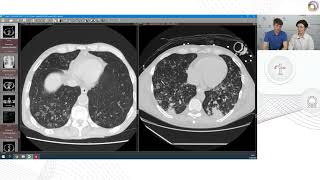

А это точно туберкулёз? Дифференциальная диагностика изменений в лёгких. Фтизиатр и рентгенолог

П.В. Гаврилов - Диссеминированный туберкулез легких: скиалогическая картина

Профессор Сперанская А.А.: Лучевая диагностика туберкулеза органов дыхания

Одиночные очаги в легких: критерии дифференциальной диагностики